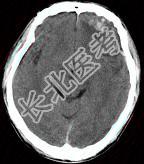

- 单项选择题成年男性,外伤后一小时, CT检查如图,最可能的诊断是 ( )

A、脑挫裂伤

B、脑转移瘤

C、钙化灶

D、脑膜瘤

E、脑出血